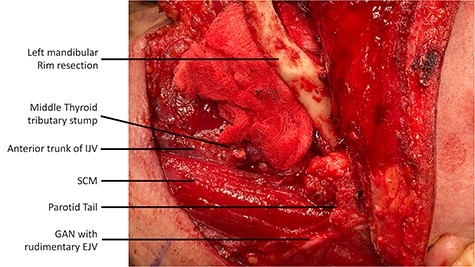

Intraoperatively, during the ND, a rudimentary only external jugular vein (EJV) was identified. Whilst developing the platysma flap, a large venous vessel was identified antero-medially to the SCM and preserved (Fig. 1). This was subsequently found to represent the anterior trunk of the duplicated IJV. Then, when developing the levels II–III–IV of the ND specimen the posterior segment of the IJV was identified and preserved. The course of IJV duplication began at level II under the posterior belly of the DGM. The bifurcation continued to level IV, beneath the omohyoid muscle. Both segments were ~9 cm in length and all the main IJV tributaries (lingual, facial and middle thyroid veins) were draining into the anterior segment (Fig. 2). The space between the two segments was occupied by the common carotid artery, its bulb and its bifurcation. The SAN was found to be running under the two IJV trunks (Fig. 3).

The duplicated IJV is demonstrated post-neck dissection and after the flap inset (recipient facial artery and pedicle of RFFF is shown).

Once the ND and the cancer ablation were completed the RFFF venous system (one vena comitans and the cephalic vein) were anastomosed end-to-end to the preserved and prepared tributaries of the anterior IJV trunk. The patient marked an uneventful postoperative course.